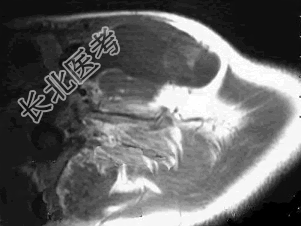

- 多项选择题37岁女性,左侧颈部肿块渐进性增大, 无压痛,局部皮温不高, CT、MRI扫描如图所示,请选择正确的描述或诊断 ( )

A、CT发现左侧颈后三角区可见低密度肿块影

B、增强扫描未见强化

C、MRI的T

WI呈低信号D、MRI的T

WI呈高信号,其内可见分隔E、考虑为淋巴管囊肿